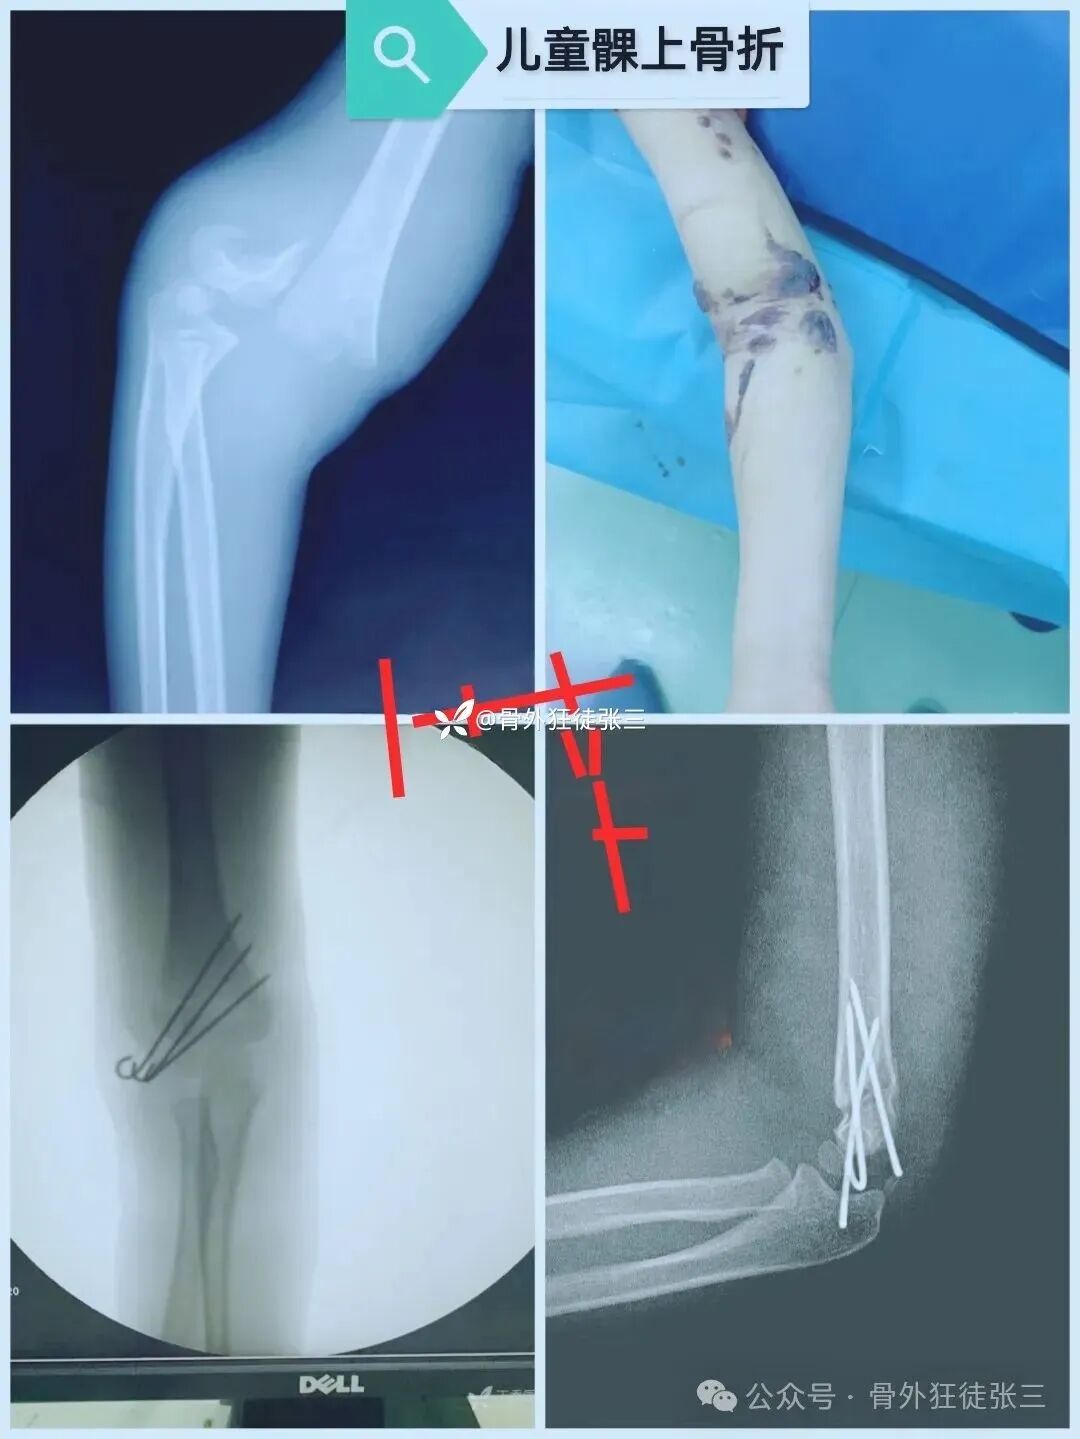

儿童髁上骨折

我们的经验:

一般选择急诊处理

臂丛麻醉下

手法复位

优先桡侧三枚针,发散固定

(个人觉得与肱骨干呈30-45-60度,最佳)

复位方法偷师自湘潭中医院曹谦老师

不吃射线

不穿铅衣

儿童做好防护

透视次数6-20次

复位次数1-3次

手术时间10-20分钟

克氏针推荐1.5mm

术后2周石膏

无需使用抗生素

术后观察肢体肿胀情况和手指血运

1-3天可出院,上学

2周来院更换为肘关节活动支具

指导功能锻炼

4周来院复查骨折愈合情况

低龄儿童4周能拔针

大龄儿童6周能拔针